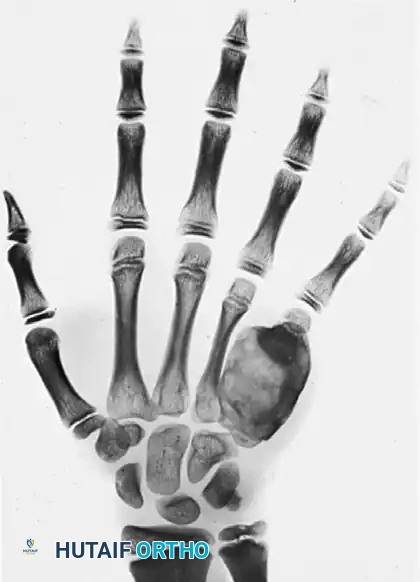

* Radiographic Appearance: Osteoblastomas are highly expansile. They produce gross metacarpal or phalangeal deformities. Radiographically, they exhibit a characteristic "ground-glass" appearance due to the varying degrees of matrix ossification. Despite tremendous expansion, the cortical shell typically remains intact, though it may become paper-thin and cause pressure deformities on adjacent bones.

Expanding intraosseous tumor of the fifth metacarpal exhibiting a ground-glass appearance. Note the intact cortical shell causing pressure deformity on the adjacent fourth metacarpal.